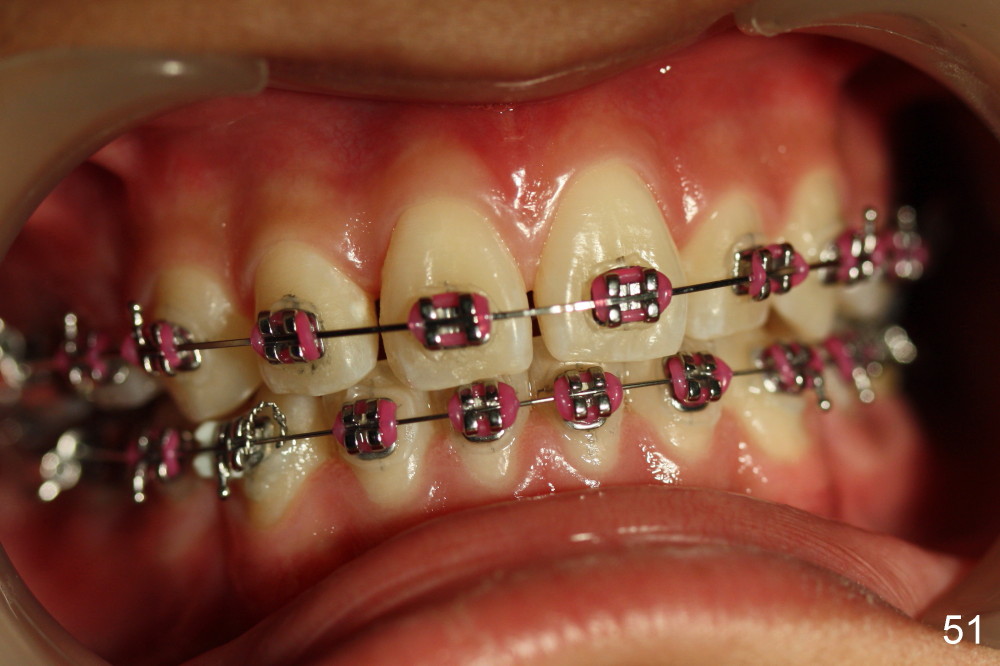

A 13-year-old boy has severe crowding (Fig.1-5). Four of the first bicuspids were extracted on 02/17/2014. Full mouth brackets or bands (except #18) were placed on 03/27/2014. Alignment improved 2 months later (Fig.11, 05/24/2014). The upper 18 ss wire was modified (Fig.12), and fixed with alastiks (Fig.13,14). One month later (07/01/2014), local alignment also improved (Fig.15); the upper modification is confined to one tooth.

Four and a half months post bracketing (Fig.21-25), what do you find and what should be done next?